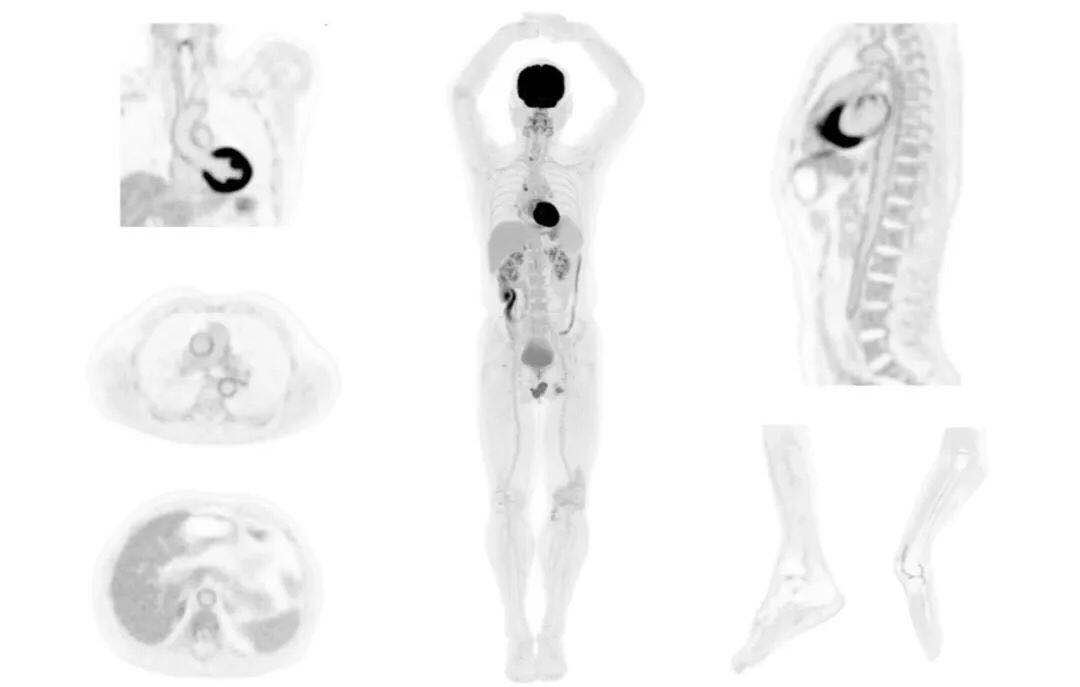

uExplorer探索者不再局限于傳統(tǒng)靜態(tài)代謝過程3D成像,而是在此基礎(chǔ)上新增一個維度——時(shí)間,從而實(shí)現(xiàn)4D全景成像。

注射總劑量為7.8mCi,14分鐘全身采集時(shí)間,在擁有超高靈敏度與超高分辨率的uEXPLORER上,即可得到展示顯示人體諸多精細(xì)結(jié)構(gòu)的高清三維圖像。

注射總劑量為7.8mCi,注射后1.6小時(shí),基于uEXPLORER探索者掃描1分鐘的圖像

注射總劑量為0.67 mCi FDG(低于常規(guī)劑量的十分之一),基于uEXPLORER探索者掃描15分鐘的圖像

注射總劑量為6.9mCi,注射后10小時(shí),基于uEXPLORER探索者掃描14分鐘的圖像